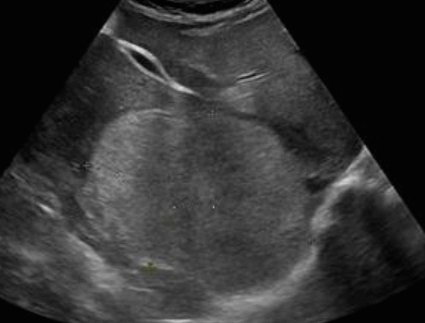

US finding

- 무에코(anechoic)

- 경계가 분명하다(sharp margin)

- 후방음향증강(posterior enhancement)

- 측방음영(lateral shadow)

simple cyst ② polycystic liver disease (PLD)